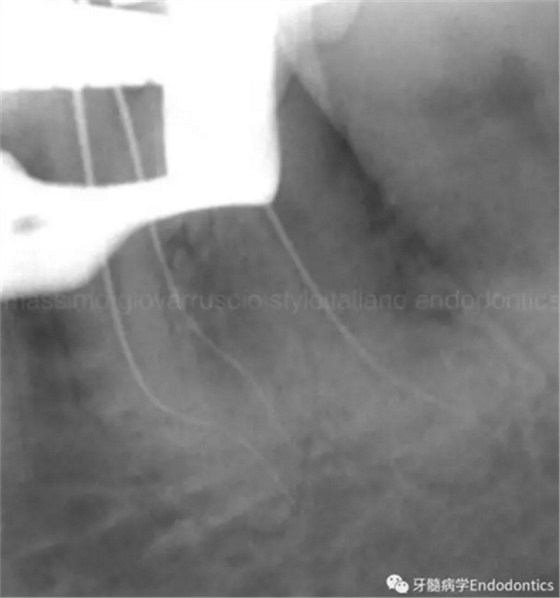

圖3.存在細(xì)小狹長(zhǎng)、可能多維的復(fù)雜根管解剖時(shí),使用10號(hào)K銼不可能立即疏通根管到達(dá)根尖止點(diǎn)。隨后醫(yī)生應(yīng)嘗試使用更小的銼探查以達(dá)到根尖。但是,通常不需要使用6號(hào)和8號(hào)K銼對(duì)到達(dá)根尖的引導(dǎo)通道進(jìn)行擴(kuò)大,除非是特別困難的病例。

圖4.根尖孔通常比10號(hào)K銼大,因此感到任何阻力時(shí)可能是因?yàn)楦艿膹澢虿灰?guī)則。因此,有效的建立可重復(fù)的引導(dǎo)通道的方法應(yīng)是使用10號(hào)K銼逐步擴(kuò)大開放根管,此時(shí)也將產(chǎn)生臺(tái)階或根管堵塞的可能性降到最低。